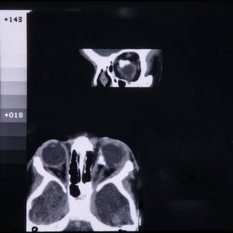

CT Scan of Brain Showing Cerebral Hypoplasia

CT Scan of Brain Showing Cerebral Hypoplasia

Feb 20 2015 by H. Michael Lambert, MD

CT scan of brain showing cerebral hypoplasia

Condition/keywords: cerebral hypoplasia, CT scan, linear nevus sebaceous syndrome